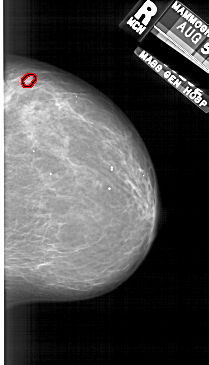

A_1689_1.RIGHT_MLO

RIGHT_MLO LINES 6211 PIXELS_PER_LINE 3481 BITS_PER_PIXEL 12 RESOLUTION 43.5 OVERLAY

FILE: A_1689_1.RIGHT_MLO.OVERLAY

TOTAL_ABNORMALITIES 1

ABNORMALITY 1

LESION_TYPE MASS SHAPE OVAL MARGINS CIRCUMSCRIBED

ASSESSMENT 4

SUBTLETY 3

PATHOLOGY BENIGN

TOTAL_OUTLINES 1

BOUNDARY